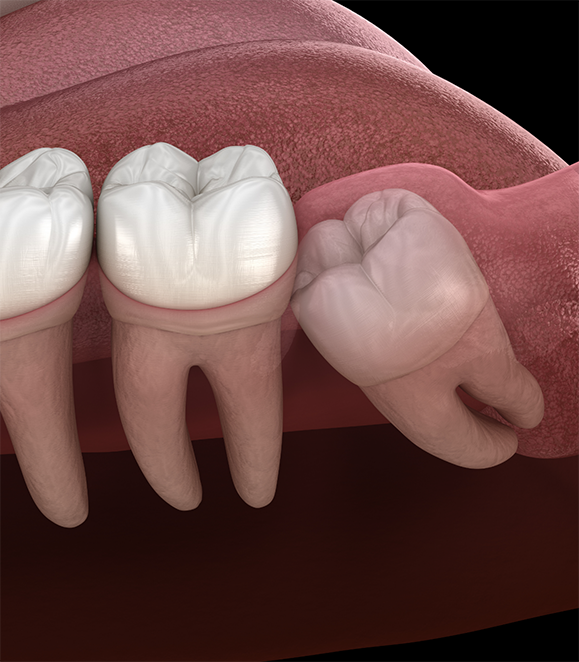

The wisdom teeth are the last set of teeth to come into the mouth, usually appearing between the ages of 16-25. However, most people don’t have enough room for them. So they become trapped within the gum and bone (impacted) or press on the nearby teeth, which can lead to pain, infection, bone loss, and other unpleasant symptoms. As a board-certified oral surgeon in Medford with significant experience removing wisdom teeth, Dr. Keyser is able to prioritize a patient’s comfort before, during, and after the procedure. If you or your teen is experiencing wisdom teeth woes, there’s no need to wait for relief—call today to schedule an appointment.

There are two different approaches Dr. Keyser can take for wisdom tooth extraction based on the situation:

Surgical: If the wisdom teeth are partially stuck in the gum and bone, or impacted, then a minor surgery is necessary. With this, any tissue that blocks access to the tooth is moved, and then the tooth is delicately extracted, often in pieces to prevent excessive force on the jaws and to preserve the surrounding anatomy such as the nerves and sinus cavity. The gums are then replaced into their customary position.